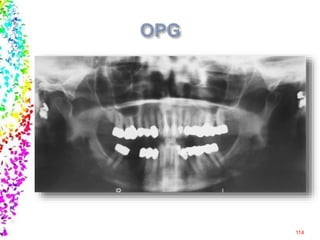

Sialography, Cephalometry, OPG, MRI, CT scan etc

Hematological investigations Urine analysis Biochemicalinvestigations Radiological investigations Histopathological investigations Microbiological investigations Sialography, Cephalometry, OPG, MRI, CT scan etc